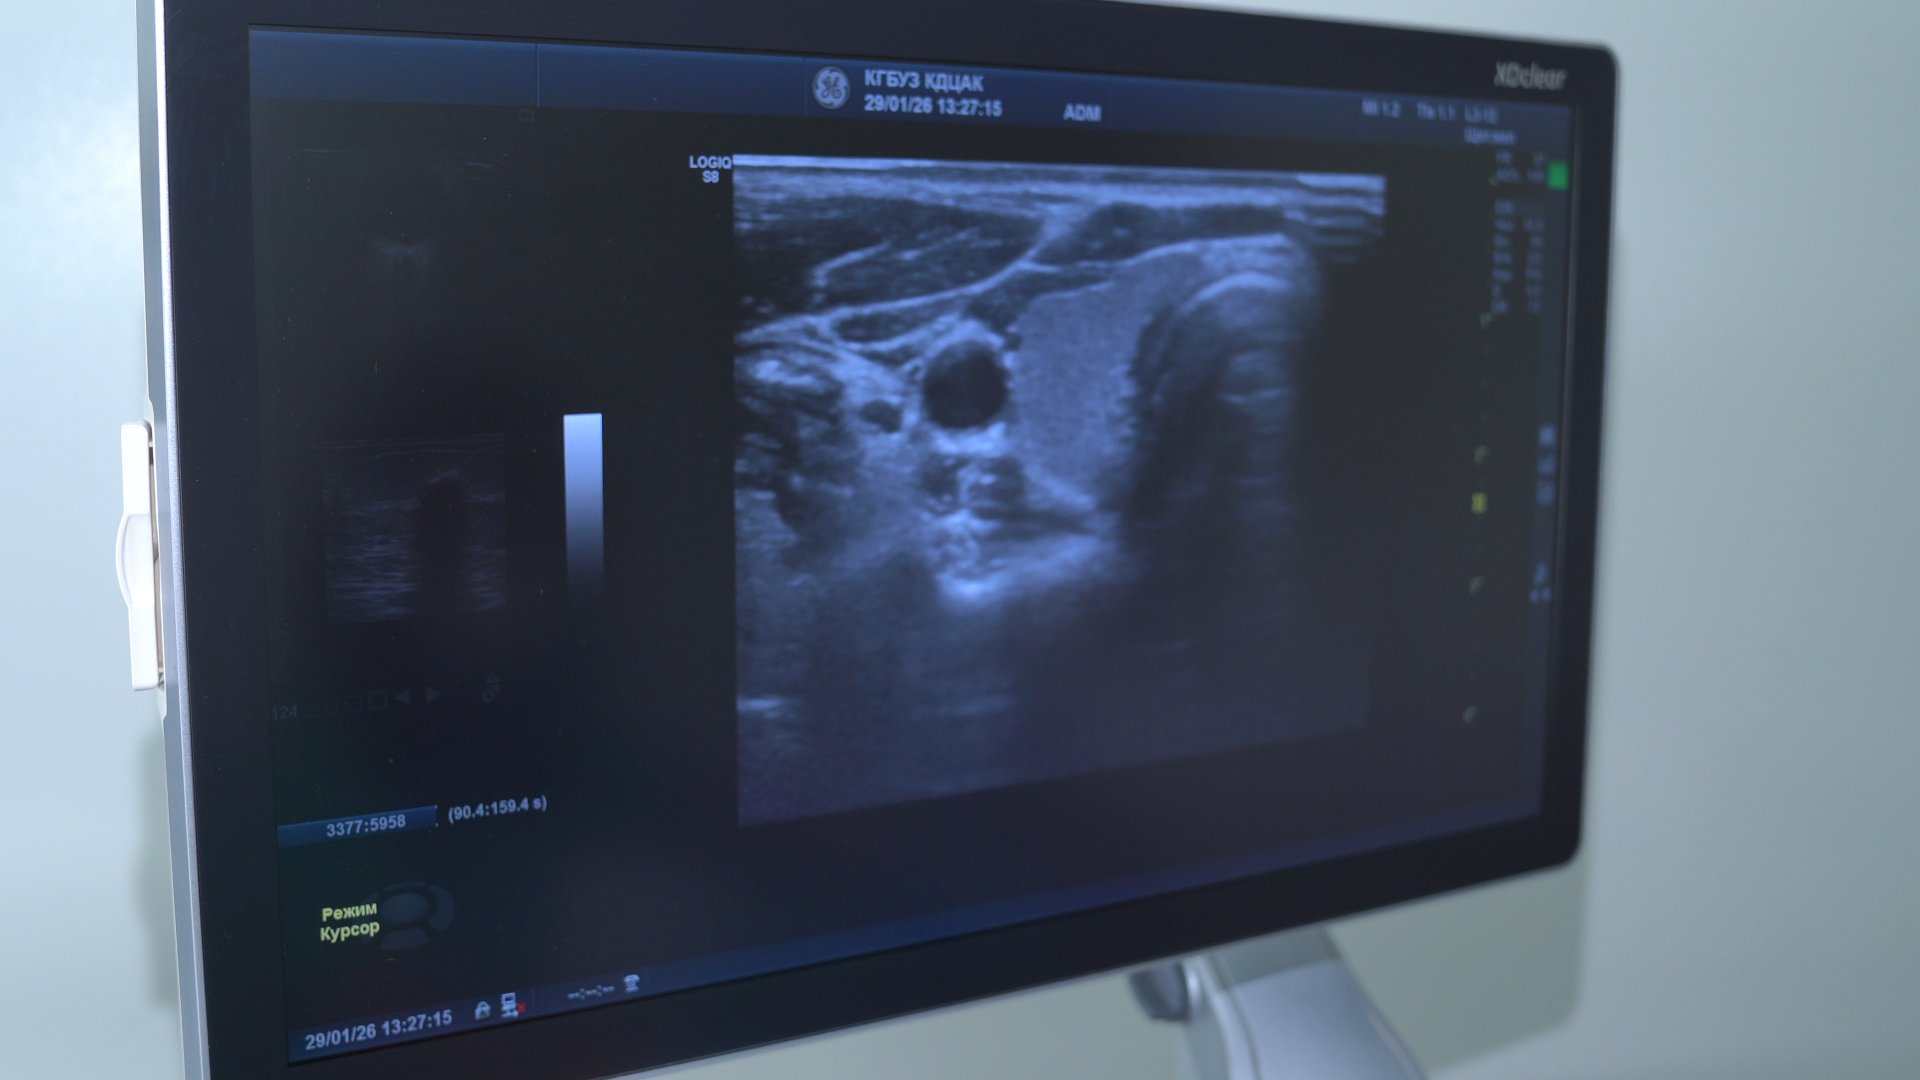

Для того чтобы диагноз был максимально точным, центр амбулаторной онкологической помощи в диагностическом центре постоянно оснащается новыми лабораторными мощностями и оборудованием.